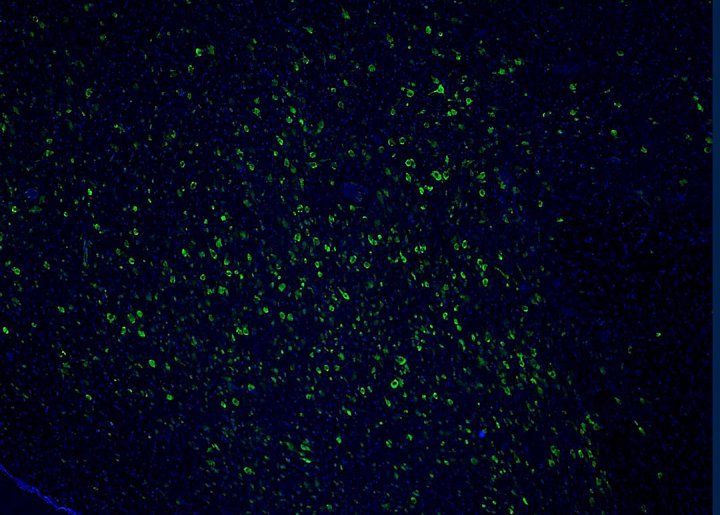

Oh describes these neurons as “extremely smart” because they can produce an array of neurotransmitters and can excite, inhibit, and modulate other nerve cells.

“It’s a small number of neurons but their computational capabilities are incredible,” Oh said. “When these cells are affected by disease, it can have a huge effect on sleep.”

To determine what’s contributing to the degradation of these neurons in Alzheimer’s, the researchers looked at the brains of 33 patients with Alzheimer’s, 20 with PSP, and 32 volunteers who’d had healthy brains through the end of life.

Images by Grinberg Lab